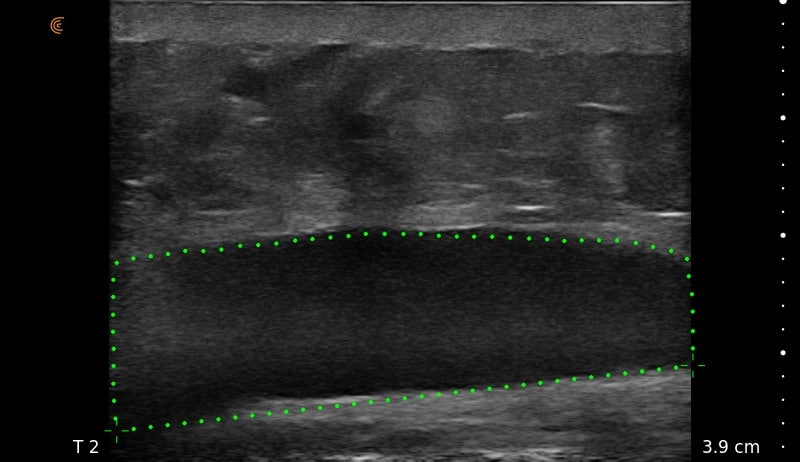

Ultrasound Imaging is very useful clinical tool to assess patient’s anatomy. In the past, ultrasound imaging was done primarily by radiologists, but is now being employed by many clinical specialties. Ultrasound use by Plastic Surgeons, however, is relatively new. Dr. Wigod has found ultrasound imaging to be a particularly valuable addition to physical exam and provides this service to his patients. Ultrasound imaging is especially useful to assess breast implants for problems such as ruptures, capsular contracture, and fluid collections. Dr. Wigod also uses ultrasound to examine other body areas and to help guide nerve blocks. Surgeon performed ultrasound does not replace radiologist performed imaging and is not for cancer screening.